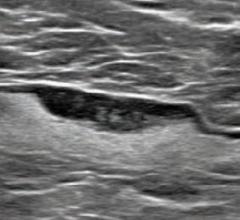

Breast density, or fibroglandular density, is found through breast imaging and compares the amount of fat to the amount of tissue.